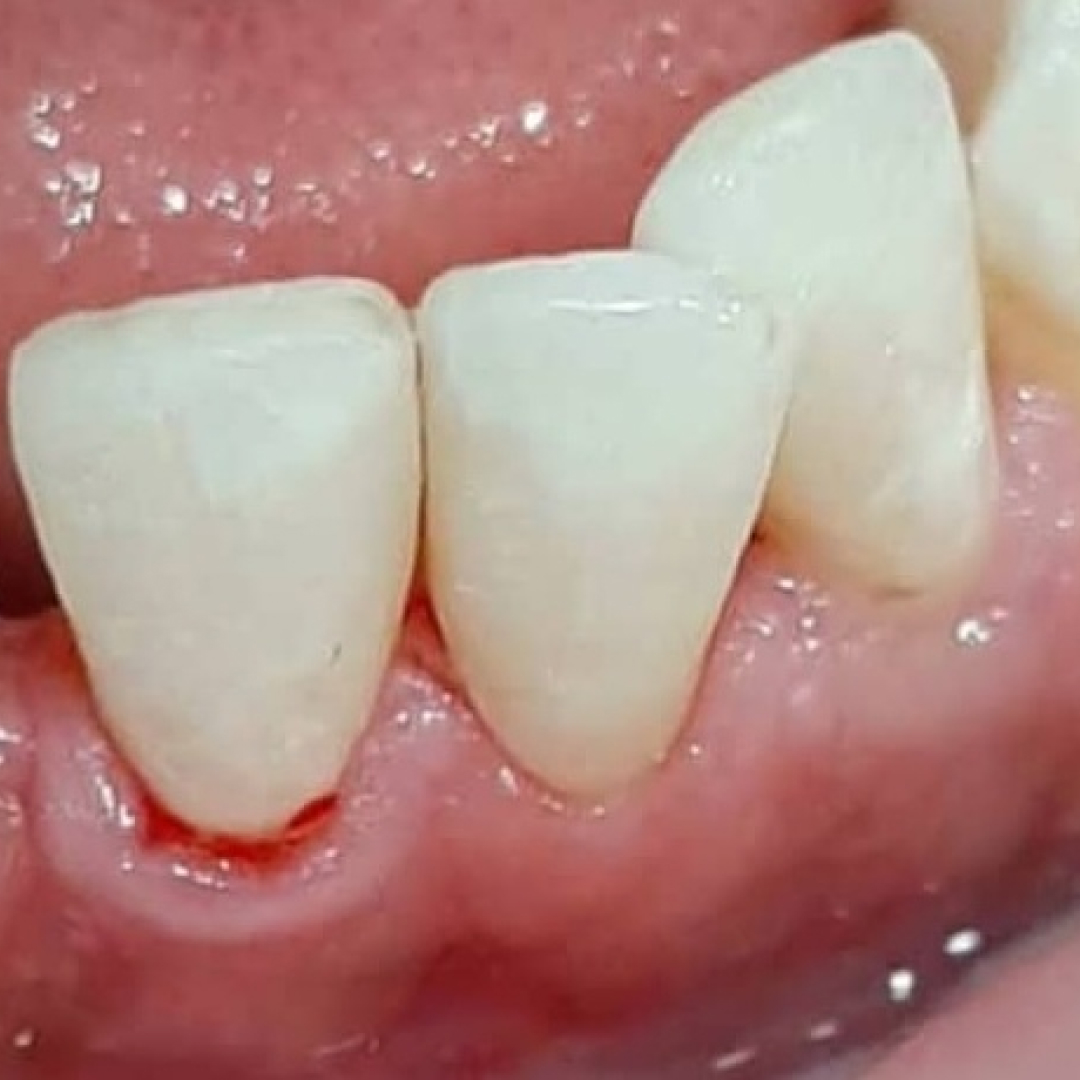

В «Стоматологию комфорта» обратилась пациентка с жалобами на эстетические дефекты 3.2, 3.1, 4.1 зубов. В процессе осмотра врач Серебрякова Мария Борисовна диагностировала хронический средний кариес зубов. Врач сделала заключение о целесообразности лечения и реставрации зуба при помощи композита Estelite.

Высокопрочный материал Estelite имеет отличные эстетические и функциональные показатели. Пломбировочная масса устойчива к истиранию и имеет широкий спектр оттенков — более 20 тонов. При правильной нагрузке и соблюдении правил гигиены полости рта срок службы пломбы — до 10-15 лет.